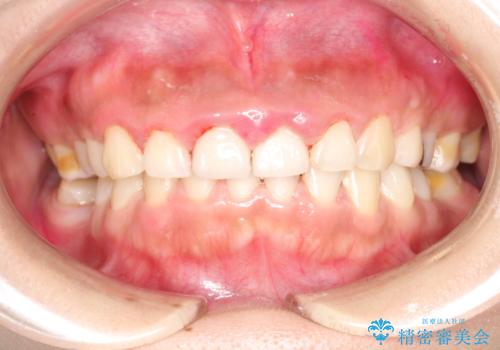

終了時

かなり久しぶりの歯科医院との事で、全体的に古くからの歯垢・歯石が多く付着していたため、自費クリーニング(PMTC)60分コース・歯周ポケット検査(保険適応)を行いました。

磨き残しが放置されると、そこで病原菌が繁殖し始めます。よって歯肉に炎症が生じ、歯周病の原因になることがあります。

定期的に、歯周病検査や専門的なクリーニングをすることで、早期発見につながります。